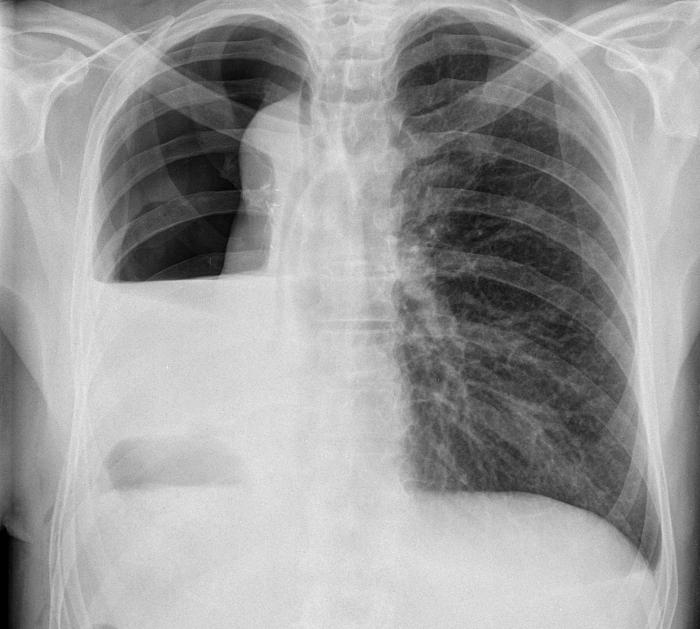

Рентгенологические изображения и синдромы патологии легких

Раздел: Кадры-подсказки